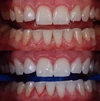

Zirkonyum uygulamalar

Porselen uygulamaları

Laminate veneer